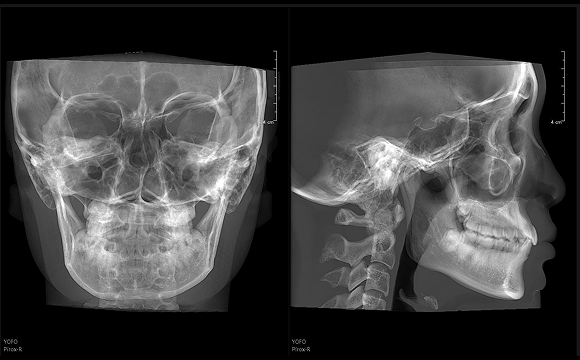

只需一次单圈扫描即可获得CT、3D全景和3D正/侧位影像,并能同时生成3D TMJ视图

提高诊疗效率,避免过度检查,减少患者所受的辐射

• 3D 正侧位

3D 正侧位

16×15cm

非拼接大视野

28lp/cm

高精准

Physics-driven系列伪影校正算法

实现高清精准成像

物理驱动

伪影校正算法